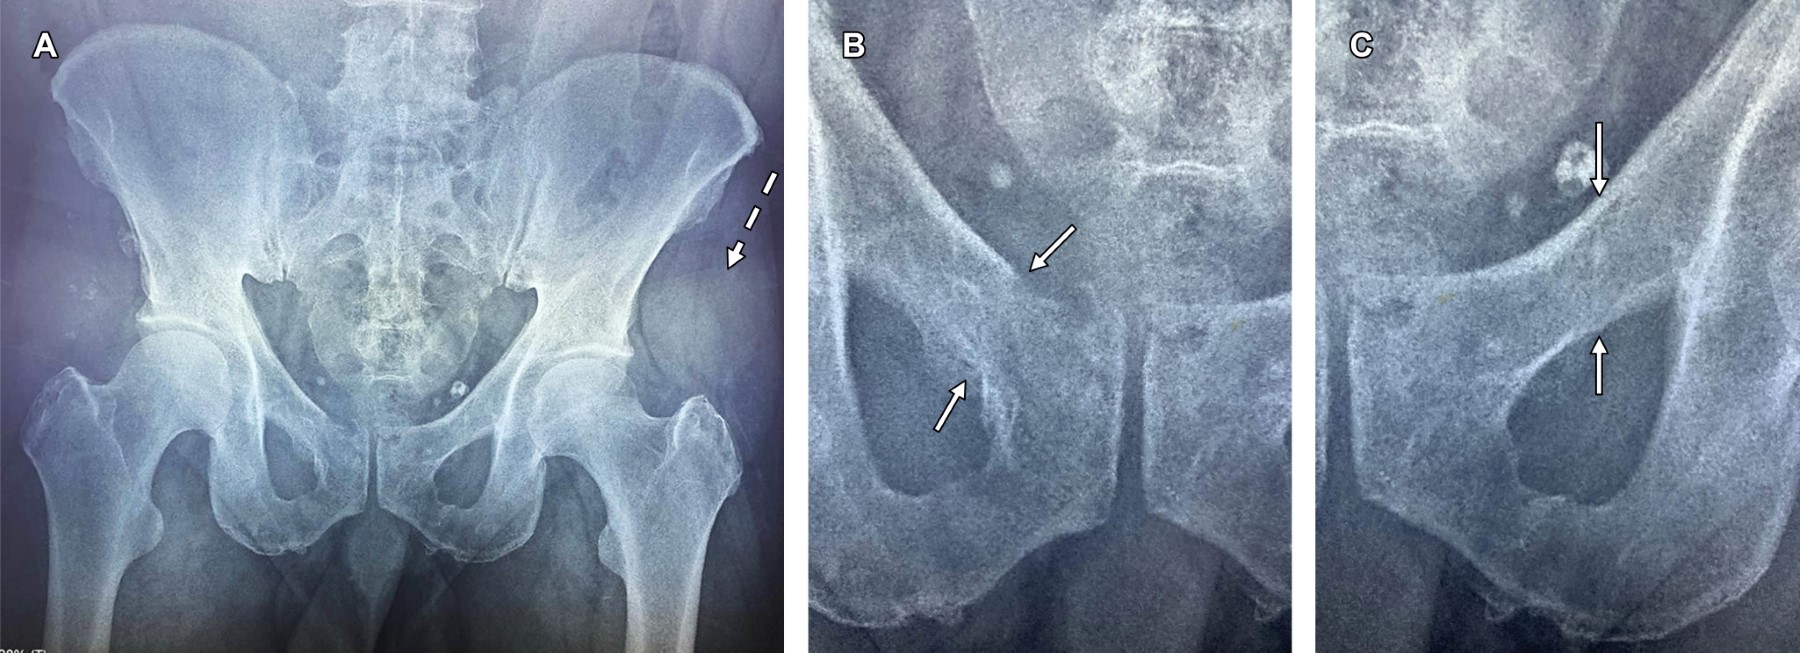

Masculino de 53 años, quien sufrió una caída desde una altura de tres metros, impactando contra piso de tierra sobre el trocánter mayor izquierdo. Presentó dolor intenso en la región del trocánter mayor izquierdo y dolor inguinal bilateral. Acudió al servicio de urgencias, donde se le realizaron estudios radiográficos; sin embargo, pasaron desapercibidas fracturas de las ramas ileopúbicas bilaterales.

Acudió al servicio de rehabilitación un mes después. A la exploración física se observó equimosis en la región del trocánter mayor, dolor a la digitopresión en el pubis y en las ramas ileopúbicas de manera bilateral, así como limitación por dolor en la rotación interna de ambas articulaciones coxofemorales. La revisión de la radiografía inicial de pelvis mostró fracturas no desplazadas de ambas ramas ileopúbicas, correspondientes a una lesión estable tipo A (Figura 1).

Figura 1